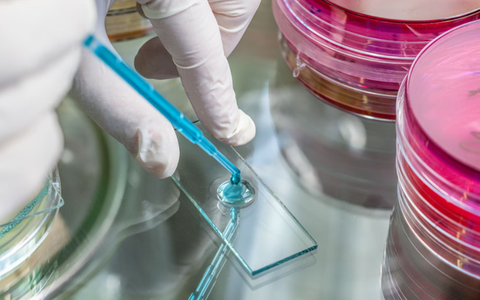

Các ‘nghiên cứu lâm sàng’ và ‘thử nghiệm lâm sàng’ là bằng chứng khoa học không thể thiếu để khẳng định tính an toàn, hiệu quả và giá trị của các sản phẩm chăm sóc sức khỏe.

Việt Nam là 1 trong 7 nước được Tổ chức Y tế thế giới lựa chọn tham gia thử nghiệm lâm sàng giai đoạn 3 vắc xin ngừa lao mới. Dự kiến thử nghiệm lâm sàng sẽ được tổ chức tại TP.HCM, Đà Nẵng, Bệnh viện Phổi trung ương vào đầu năm 2024.